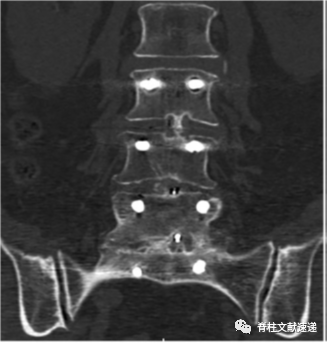

L3椎体可见明显的“双边征”(螺钉被周围硬化骨包绕)